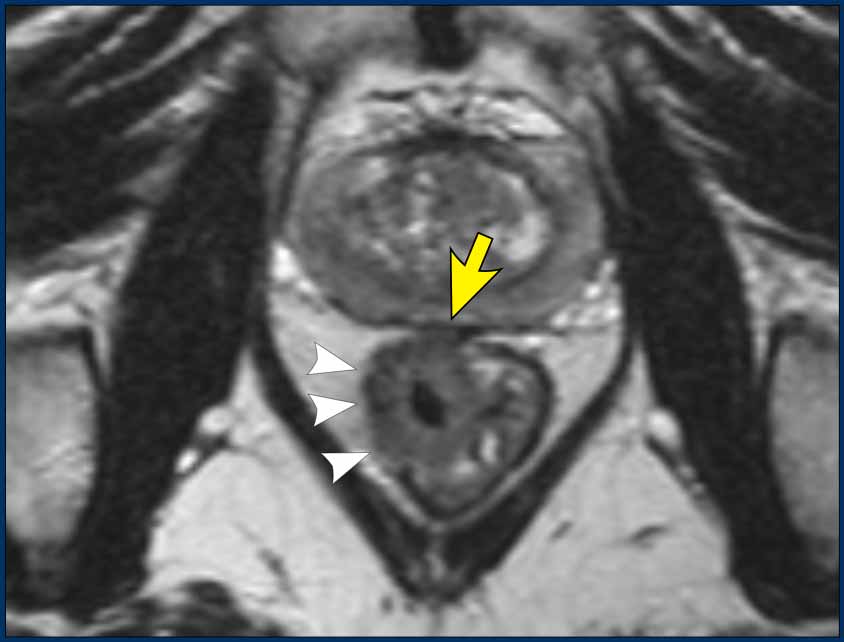

Pitfall: Assessing EMVI in tumors with massive extramural growth

In large T3cd-4 tumors with extensive extramural extension into the perirectal fat, a practical approach is to classify these as EMVI+.

In the example shown, the tumor extends into the perirectal fat from 3 to 5 o’clock, obliterating the mesorectal fat in this region.

While individual vessel involvement may not be discernible, it is reasonable to assume that vessels in this area are completely invaded by the tumor.

The dashed lines indicate the potential location of vessels.